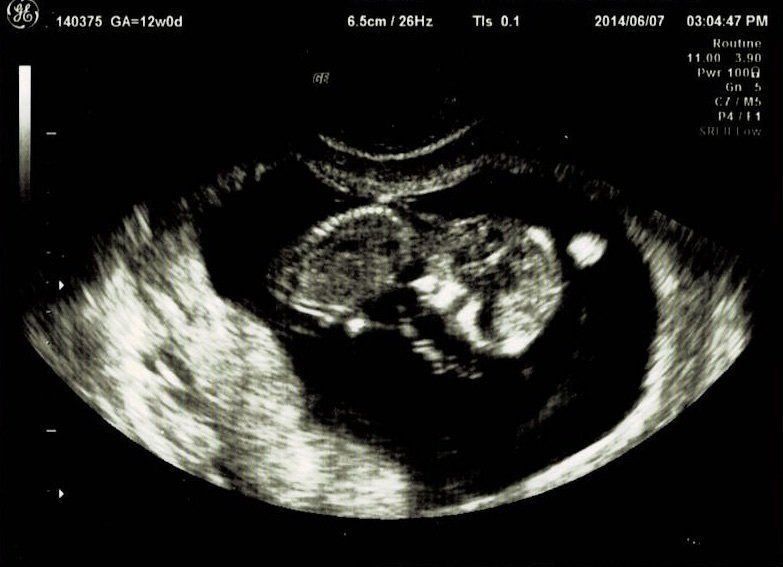

妊娠12週目エコー写真

つわり真っ盛り。しかし、おなかはまだ大きくありません。この日は採血をして、麻疹、風疹などの抗体があるか、梅毒の反応がないかなどの妊娠前期検査をしてもらいました。赤ちゃんはきちんと手足が見えて驚きました。さらには背骨まで確認できました。改めておなかの中に人間がいるという感慨がわいて、不思議な気持ちに。ガイコツみたいなエコーでもかわいいと感じました。